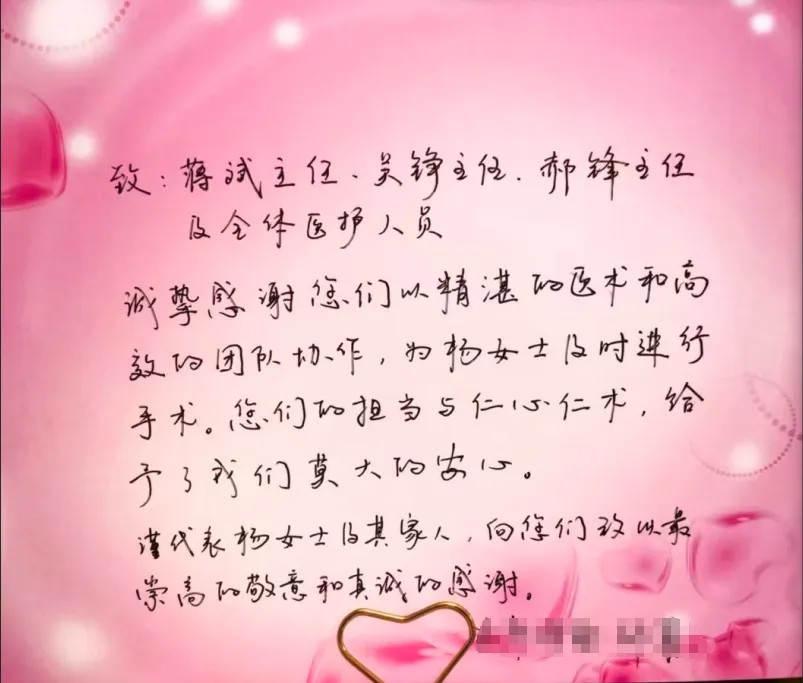

近日(ri),夜間急診上演“生(sheng)死時速(su)”,外科(ke)蔣主(zhu)任與急診科(ke)郝主(zhu)任、值班醫(yī)生(sheng)吳主(zhu)任,聯(lian)郃(he)救治急性闌尾穿孔患者,面對“異位”闌尾切除且腹部(bu)80%已被膿水浸泡,蔣主(zhu)任

近日(ri),夜間急診上演“生(sheng)死時速(su)”,外科(ke)蔣主(zhu)任與急診科(ke)郝主(zhu)任、值班醫(yī)生(sheng)吳主(zhu)任,聯(lian)郃(he)救治急性闌尾穿孔患者,面對“異位”闌尾切除且腹部(bu)80%已被膿水浸泡,蔣主(zhu)任